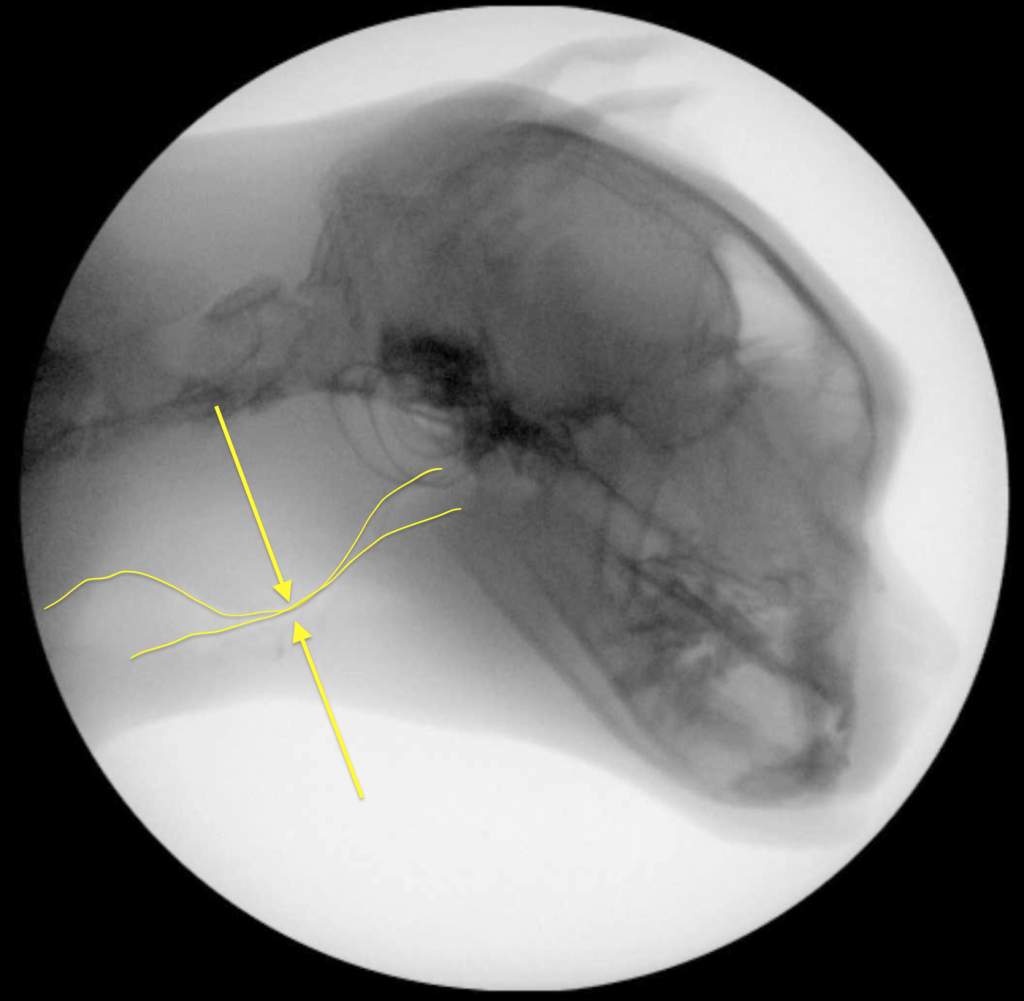

Коллапс обычно происходит во время вдоха, следовательно, это не длительное, а динамическое отклонение. Динамический назофарингеальный коллапс может быть как первичной, так и вторичной патологией5. У людей ДНФК был признан основной причиной синдрома обструктивного апноэ во сне (англ. obstructive sleep apnea syndrome; OSAS), однако в ветеринарии мелких домашних животных это состояние описывается редко, особенно у кошек5. Несмотря на сходные механизмы обструкции носоглотки у людей, собак и кошек, динамический коллапс у людей преимущественно проявляется во время сна7,8 в отличие от кошек и собак, у которых наиболее выраженные приступы одышки наблюдаются во время физической нагрузки или стресса1,2,3,5. Возможно, попытки экстраполировать методы лечения данной патологии из медицины человека являются ошибочными8.Золотым стандартом для подтверждения диагноза «динамический назофарингеальный коллапс у кошек» является рентгеноскопия акта дыхания1,2,5.

Рентгеноскопия акта дыхания проводится без седации, в естественном сидячем или стоячем положении животного.

У одного пациента коллапс проявлялся только на глубоком вдохе, у остальных трех кошек – на каждом вдохе (возможно, само исследование было стрессом для животных, что провоцировало их делать глубокие вдохи).

В результате проведенных хирургических манипуляций у всех пациентов сразу после операции нормализовалось дыхание. При проведении повторной рентгеноскопии акта дыхания ни у одного пациента не наблюдалось коллапса.